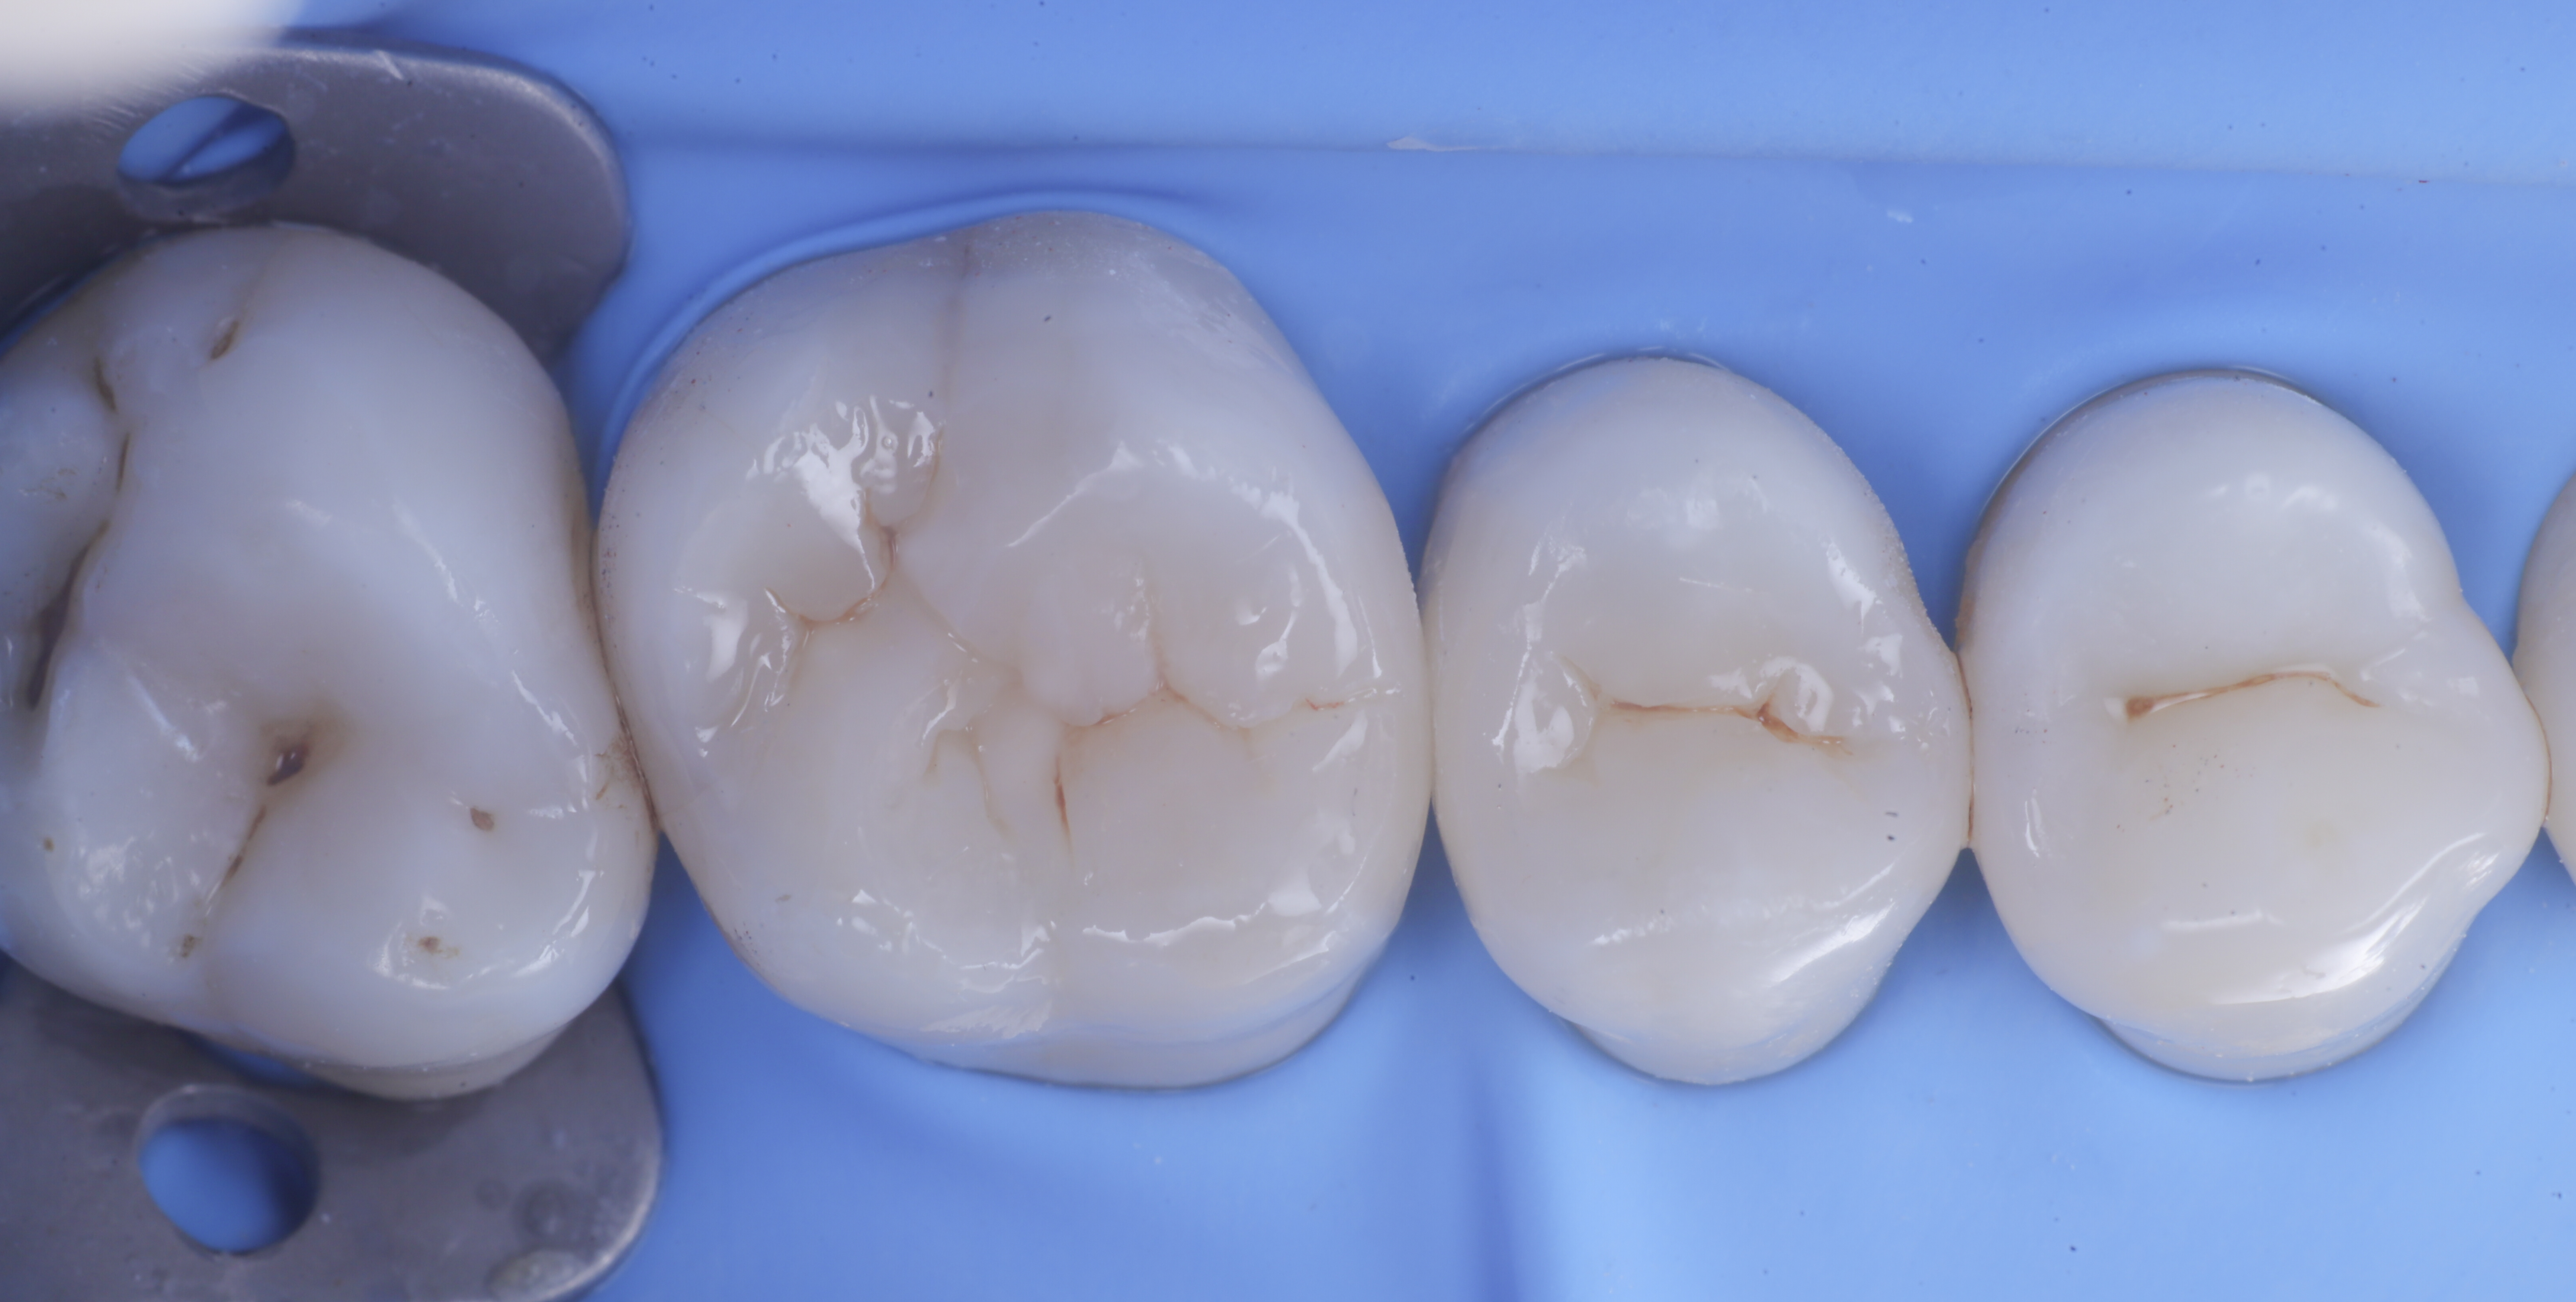

foto 8 Modellazione ed aspetto occlusale

foto 9 Modellazione ed aspetto vestibolare